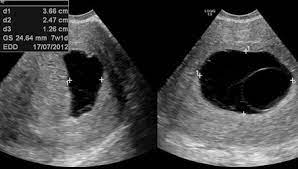

How Long Can An Anembryonic Pregnancy Last - ≥11 days after scan showing gestational sac with yolk sac, but no embryo, or 1.2.. In an anembryonic pregnancy or blighted ovum pregnancy, the sac develops, however, there is no foetus inside. Interestingly, a recent study found significantly fewer trophoblasts in women who had been diagnosed with ectopic pregnancy (an embryo attached outside the uterus) or blighted ovum. In anembryonic pregnancy, a blastocyst is formed from a fertilised ovum, but the fetal pole/embryonever develops, though histologically some fetal material can be demonstrated in most cases. Absent yolk sac when msd >8 mm on transvaginal ultrasound (tvus) 2. The patient may be asymptomatic, presenting for an early pregnancy ultrasound.

A blighted ovum occurs within the first trimester, often before a woman knows she is pregnant. See full list on mayoclinic.org Your body realises the pregnancy is not developing properly and starts to shed blood and tissue from the uterus. If you experience multiple consecutive miscarriages, talk with your doctor or other care provider to identify any underlying causes. An ultrasound will show an empty gestational sac. What are the signs and symptoms of anembryonic pregnancy? A pregnancy test may be positive because the early embryo secretes a pregnancy hormone human chorionic gonadotropin (hcg) until the embryo stops developing and fails to implant. See full list on mayoclinic.org Because a blighted ovum still makes hormones, it can show up as a positive pregnancy test. In anembryonic pregnancy, a blastocyst is formed from a fertilised ovum, but the fetal pole/embryonever develops, though histologically some fetal material can be demonstrated in most cases. See full list on mayoclinic.org May 19, 2020 · about 15 percent of all pregnancies end in miscarriage before 13 weeks of pregnancy. ≥11 days after scan showing gestational sac with yolk sac, but no embryo, or 1.2.

Mar 01, 2018 · natural expulsion may take up to two weeks. A blighted ovum eventually results in miscarriage. An ultrasound will show an empty gestational sac. A blighted ovum will cause a miscarriage usually at 7 to 12 weeks of pregnancy. May 19, 2020 · about 15 percent of all pregnancies end in miscarriage before 13 weeks of pregnancy. In an anembryonic pregnancy, however, the trophoblast attaches itself to the uterus, but the blastocyst never fully forms. Due to falling hcg levels, the clinical signs of pregnancy tend to subside. When there is no embryo seen on endovaginal scanning in a gestational sac with mean sac diameter (msd) ≥25 mm 4 or 1.

An ultrasound will show an empty gestational sac. A blighted ovum usually occurs early in pregnancy between about week 8 and week 13 sometimes before you even know you're pregnant. See full list on mayoclinic.org What are the signs and symptoms of anembryonic pregnancy? Alternatively, she may present with vaginal bleeding in early pregnancy. If you experience multiple consecutive miscarriages, talk with your doctor or other care provider to identify any underlying causes. Absent yolk sac when msd >8 mm on transvaginal ultrasound (tvus) 2. See full list on radiopaedia.org